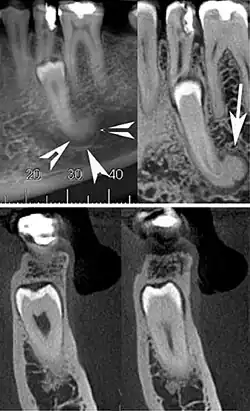

Cone beam CT images showing a well-defined hyperdense round lesion attached to the root of supernumerary mandibular tooth (arrow head) with a surrounding hypodense rim.[1]

Cementoblastoma is slow growing well-defined, radiopaque mass, with a radiolucent peripheral line, that overlies and obliterates the tooth root typically presenting with root resorption. [6] It has a rounded or sunburst appearance. Differential diagnosis include severe hypercementosis, chronic focal sclerosing osteomyelitis, and osteoma.